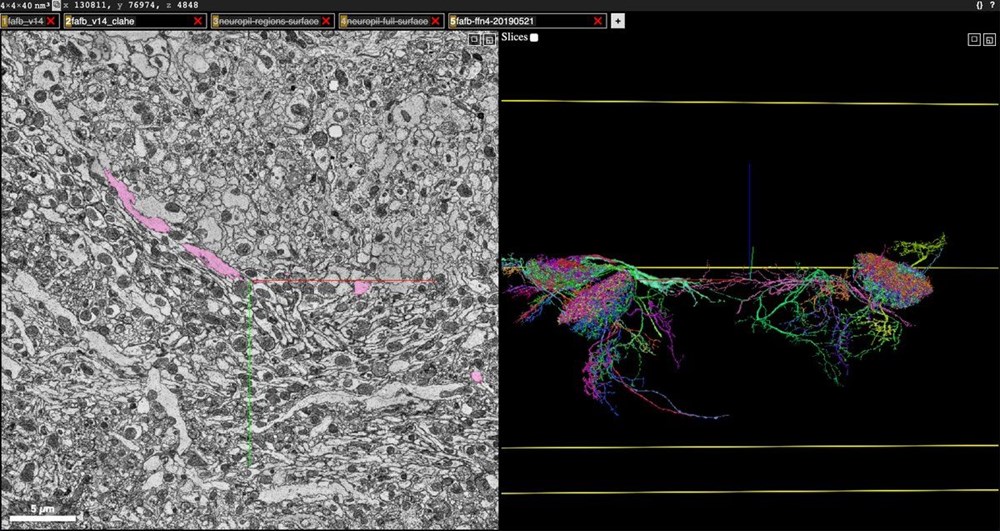

Renk kodlu harita, tek bir nörona bağlanan 4 bin aksonu gösteriyor. Aksonlar, sinir sisteminde duyusal girdileri almaktan sorumlu en temel hücreleri oluşturuyor. Sadece bir milimetre küp beyin dokusunu temsil etmesine rağmen, çalışma herhangi bir tür için bu kadar ayrıntılı olarak görüntülenen ve yeniden oluşturulan en kapsamlı harita olarak kayıtlara geçti.

Harita ayrıca, on binlerce yapılandırılmış nöron, milyonlarca nöron parçası, 130 milyon açıklamalı sinaps ve akson yapısı, dendritler ve miyelinler de dahil olmak üzere çeşitli hücre alt yapılarını da içeriyor.

Yaklaşık 4 nanometreye kadar yakınlaştırabilen bir elektron mikroskobu numuneyi taradı ve tek bir 3 boyutlu görüntüyü hacmi ortaya çıkarmak için bir araya getirilebilecek 225 milyon iki boyutlu fotoğraf oluşturdu.

Öte yandan, haritayı görüntülemek isteyenler açık kaynaklı bir çevrimiçi 3 boyutlu görselleştirme arayüzü olan Neuroglancer’ı ziyaret edebileceği ifade edildi. Neuroglancer'ın ziyaretçileri, katmanlarına göre belirli hücreleri seçerek gelen ve giden sinapsları görüntüleyebiliyor.